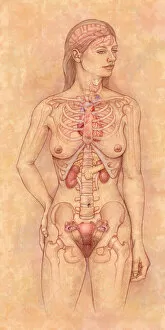

The scapula, also known as the shoulder blade, is a crucial bone in our body that plays a significant role in our mobility and stability. It forms part of the pectoral girdle and connects the upper arm to the thorax. When we examine diagrams of the bones of the hand and arm, we can see how intricately connected they are to the scapula. This connection allows us to perform various movements with precision and control. In an anterior view total shoulder joint repair image, we witness medical advancements aimed at restoring functionality to this vital joint. The intricate procedure highlights just how important it is to maintain a healthy scapula for optimal movement. Shoulder muscles artwork showcases their attachment points on the scapula, emphasizing their role in providing strength and stability during physical activities. Understanding these muscles helps us appreciate their contribution to everyday tasks like lifting or throwing. A front view of female anatomy highlighting the endocrine system reminds us that even though not directly related to the scapula, every part of our body works together harmoniously. Hormones secreted by glands within this system influence bone health and development. An anterior view of human skeletal system with labels gives us a comprehensive understanding of where exactly our scapula fits into this complex framework. It serves as an anchor point for numerous ligaments and tendons essential for proper functioning. Pictograms on an ox scapula depict ancient rituals performed to ward off danger—a testament to how cultures throughout history recognized its significance beyond mere anatomy. These artifacts remind us that humans have long understood its importance in daily life. The skeleton of an eagle after Milne-Edwards engraving demonstrates nature's adaptation at its finest—the bird's wingspan relies heavily on strong shoulder blades (scapulas) allowing it effortless flight through vast skies. Haydon's Curtius engraving captures another artistic representation showcasing human form—this time focusing on muscular structure including the scapula.